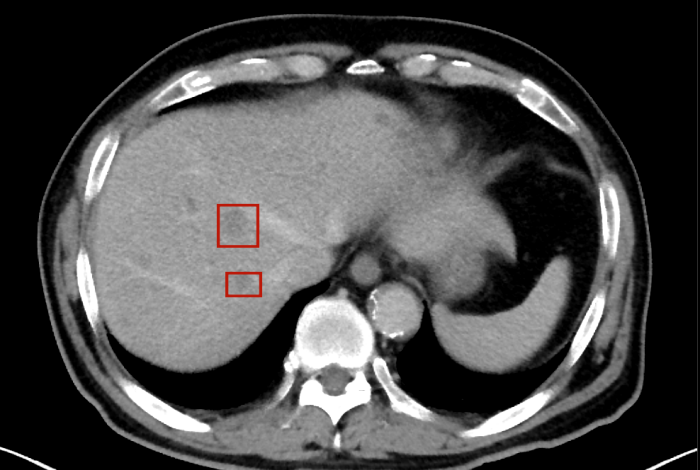

術(shù)后,萬(wàn)秀萍為黃先生做進(jìn)一步的檢查,腹部磁共振(MRI)檢查顯示:肝臟區(qū)域出現(xiàn)了轉(zhuǎn)移病灶的陰影。

轉(zhuǎn)移病灶的陰影

目前,黃先生的腫瘤活動(dòng)已得到有效抑制,肝臟轉(zhuǎn)移灶未見(jiàn)爆發(fā)性進(jìn)展,病情整體保持穩(wěn)定。